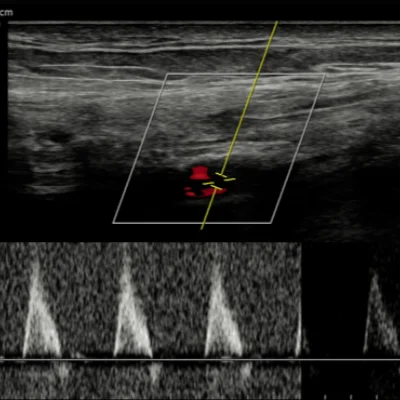

Doppler Ultrasound

Doppler studies assess blood flow in arteries and veins, helping detect

Deep vein thrombosis (DVT)

Peripheral artery disease

Carotid artery narrowing

Placental blood flow in pregnancy

These scans are crucial for vascular health and prenatal monitoring, offering dynamic insights into circulation.